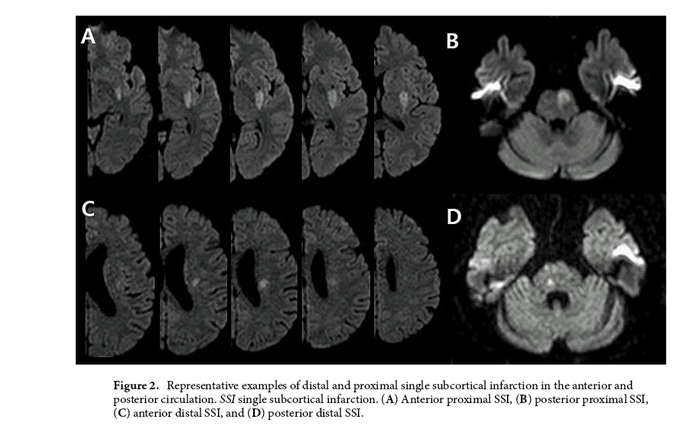

단일 피질하 경색(single subcortical infarction, 이하 SSI)은 천공 동맥 영역에서 발견되는 단일 병변의 허혈성 뇌졸중으로, 다른 기전으로 발생하는 뇌졸중과는 달리 이 환자들은 대개 경미한 신경학적 증상을 겪는다. 따라서, 초기 예후는 비교적 양호하지만 많게는 43% 환자들이 처음보다 증상이 악화하는 ‘초기 신경학적 악화(Early Neurological Deterioration, END)를 경험한다. 따라서 이 악화의 발생 기전을 규명하고 예방하는 것이 중요하다.

한편, 경색의 성장 속도와 초기 신경학적 악화의 연관성은 단일 피질하 경색의 병변 위치에 따라 다르게 해석될 수 있는데, IGV값은 모 동맥과 접촉하지 않는 원위부 SSI보다 모 동맥과 인접한 경색인 근위부 SSI에서 더 높았지만(P < 0.001) 초기 신경학적 악화 여부에 따른 IGV값의 유의한 차이가 상대적으로 원위부에서만 도드라졌다.

이 연구의 결과에 대해 신경과 남기웅 교수는 “단일 피질하 경색에서 초기 진행 여부를 결정하는 가장 중요한 인자는 초기 경색 병변의 성장과 최종 경색의 크기이다. 병변의 부피가 작은 원위부에서는 IGV값이 약간만 높아져도 신경학적 악화가 진행될 가능성이 커진다.”고 밝혔다. 또한 “이러한 초기의 신경학적 악화는 퇴원 결과와도 밀접한 관련이 있다는 것을 감안할 때, 경색의 성장 속도를 주시하는 것은 특히 원위부 단일 피질하 경색 환자에게서 임상적 의미를 가질 수 있다. 향후 전향적 연구를 통해 검증할 예정이다.”고 소감을 전했다.